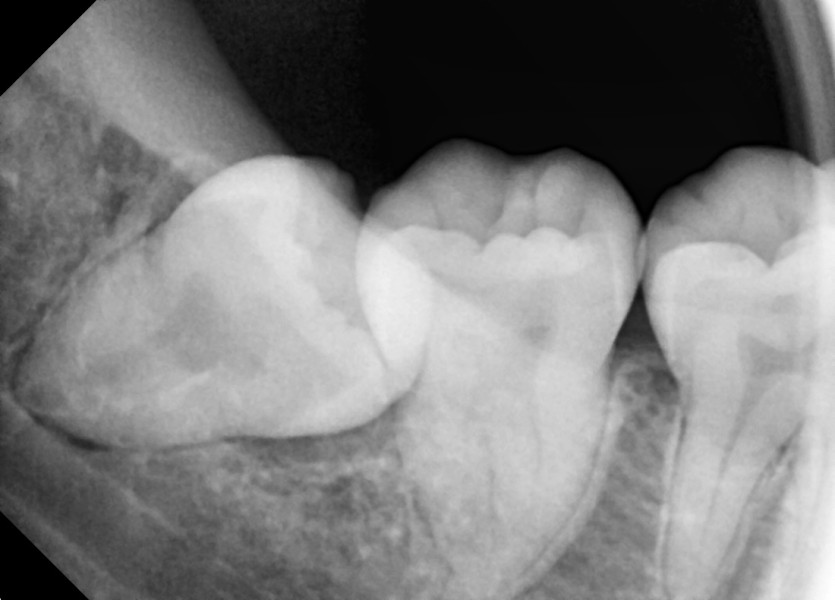

#48 사랑니 발치

구강 외과 전문의가 당일 발치했습니다.